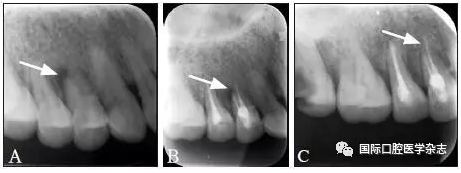

典型病例1 14牙因頸部楔狀缺損穿髓致根尖周炎,根管治療后根尖周透射區(qū)骨質(zhì)修復(fù)(圖1)。

A:初診X線片;B:充填后即刻X線片;C:13個(gè)月復(fù)查X線片。

圖 1 14牙根尖周炎經(jīng)根管治療后愈合